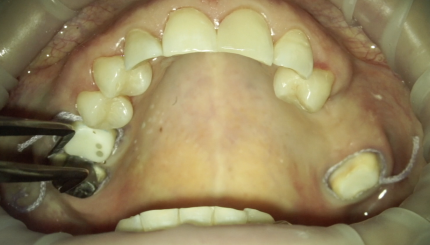

36 . локальное тангенциальное препарирование +временная коронка